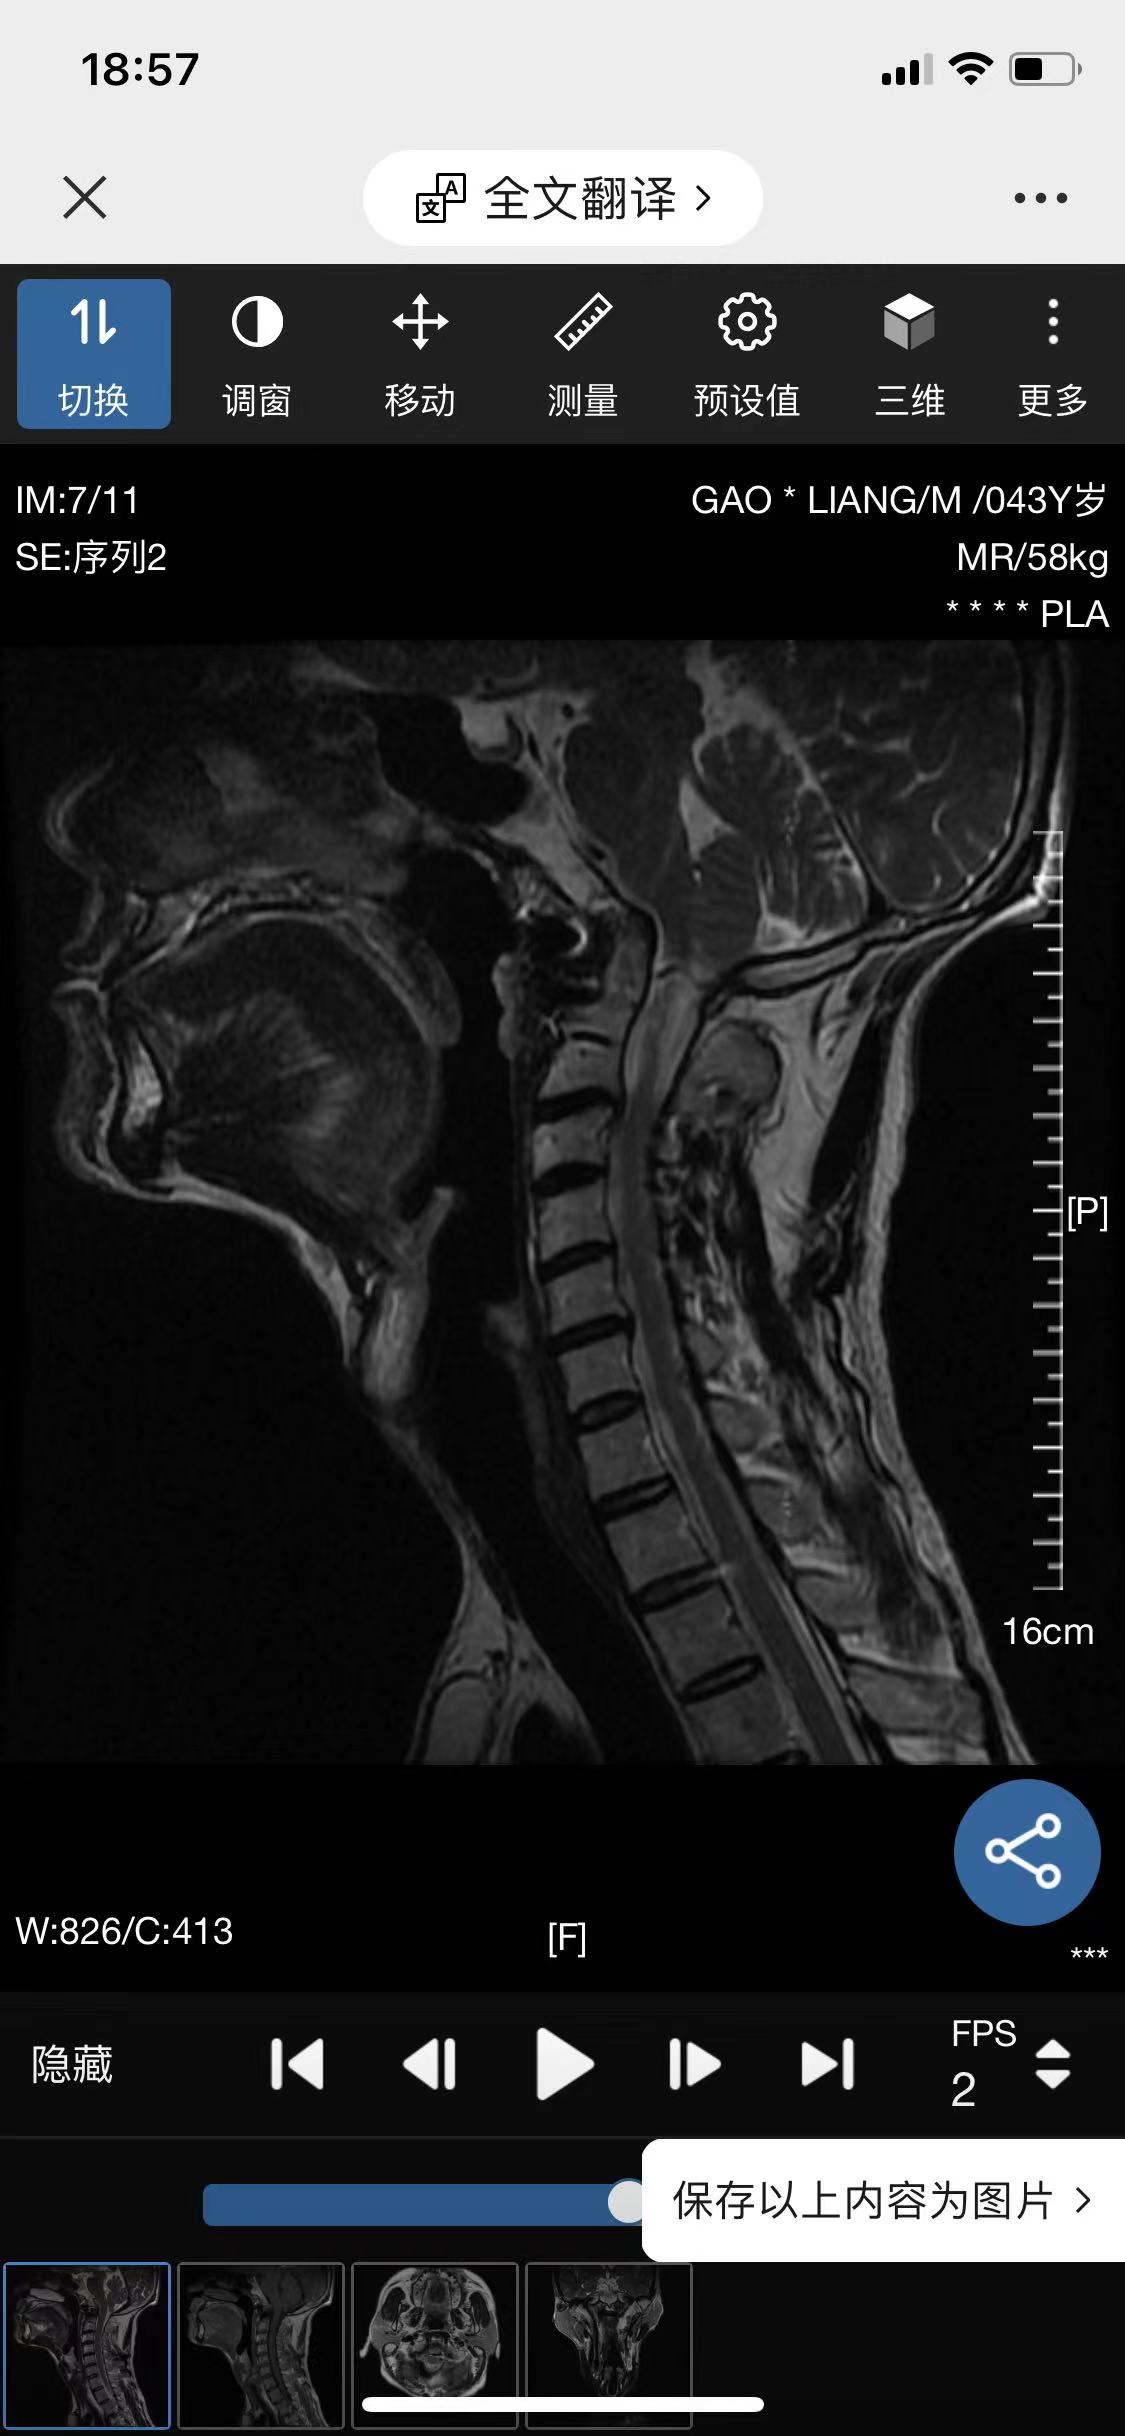

• 诊断:寰枢椎脱位

• 影像:

• 术后影像: